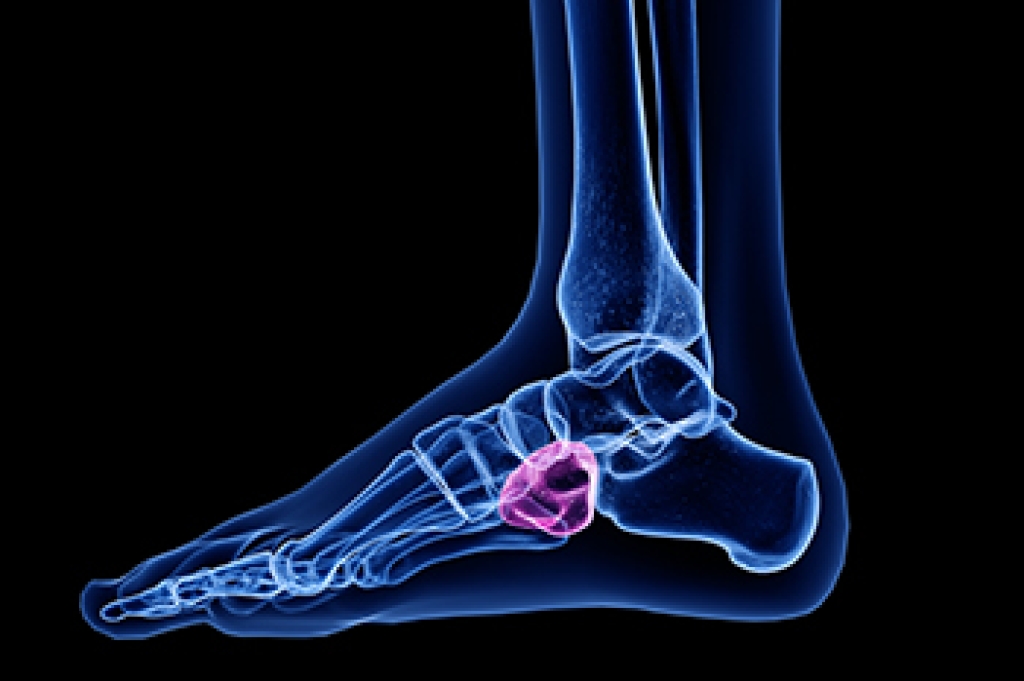

Cuboid syndrome, a lesser known but impactful foot ailment, unfolds as a condition where the cuboid bone in the foot becomes displaced, leading to discomfort and pain. The cuboid bone, situated on the outer midfoot, plays a critical role in supporting the foot's arch and facilitating movement. This syndrome occurs when the ligaments surrounding the cuboid bone undergo excessive strain or injury, causing a misalignment. Individuals engaged in activities that involve repetitive stress on the foot, such as athletes or dancers, are more prone to developing cuboid syndrome. Additionally, those with structural anomalies in foot mechanics, such as a high arch or a foot that rolls outward, known as supination, also may be at a heightened risk. If you have pain in the outer part of your foot, it is suggested that you visit a podiatrist who can properly diagnose and treat cuboid syndrome.

Cuboid syndrome, also known as cuboid subluxation, occurs when the joints and ligaments near the cuboid bone in the foot become torn. If you have cuboid syndrome, consult with one of our podiatrists from Westside Podiatry Center, LLP. Our doctors will assess your condition and provide you with quality foot and ankle treatment.

Cuboid syndrome is a common cause of lateral foot pain, which is pain on the outside of the foot. The condition may happen suddenly due to an ankle sprain, or it may develop slowly overtime from repetitive tension through the bone and surrounding structures.

A common symptom of cuboid syndrome is pain along the outside of the foot which can be felt in the ankle and toes. This pain may create walking difficulties and may cause those with the condition to walk with a limp.

Diagnosis

Diagnosis of cuboid syndrome is often difficult, and it is often misdiagnosed. X-rays, MRIs and CT scans often fail to properly show the cuboid subluxation. Although there isn’t a specific test used to diagnose cuboid syndrome, your podiatrist will usually check if pain is felt while pressing firmly on the cuboid bone of your foot.